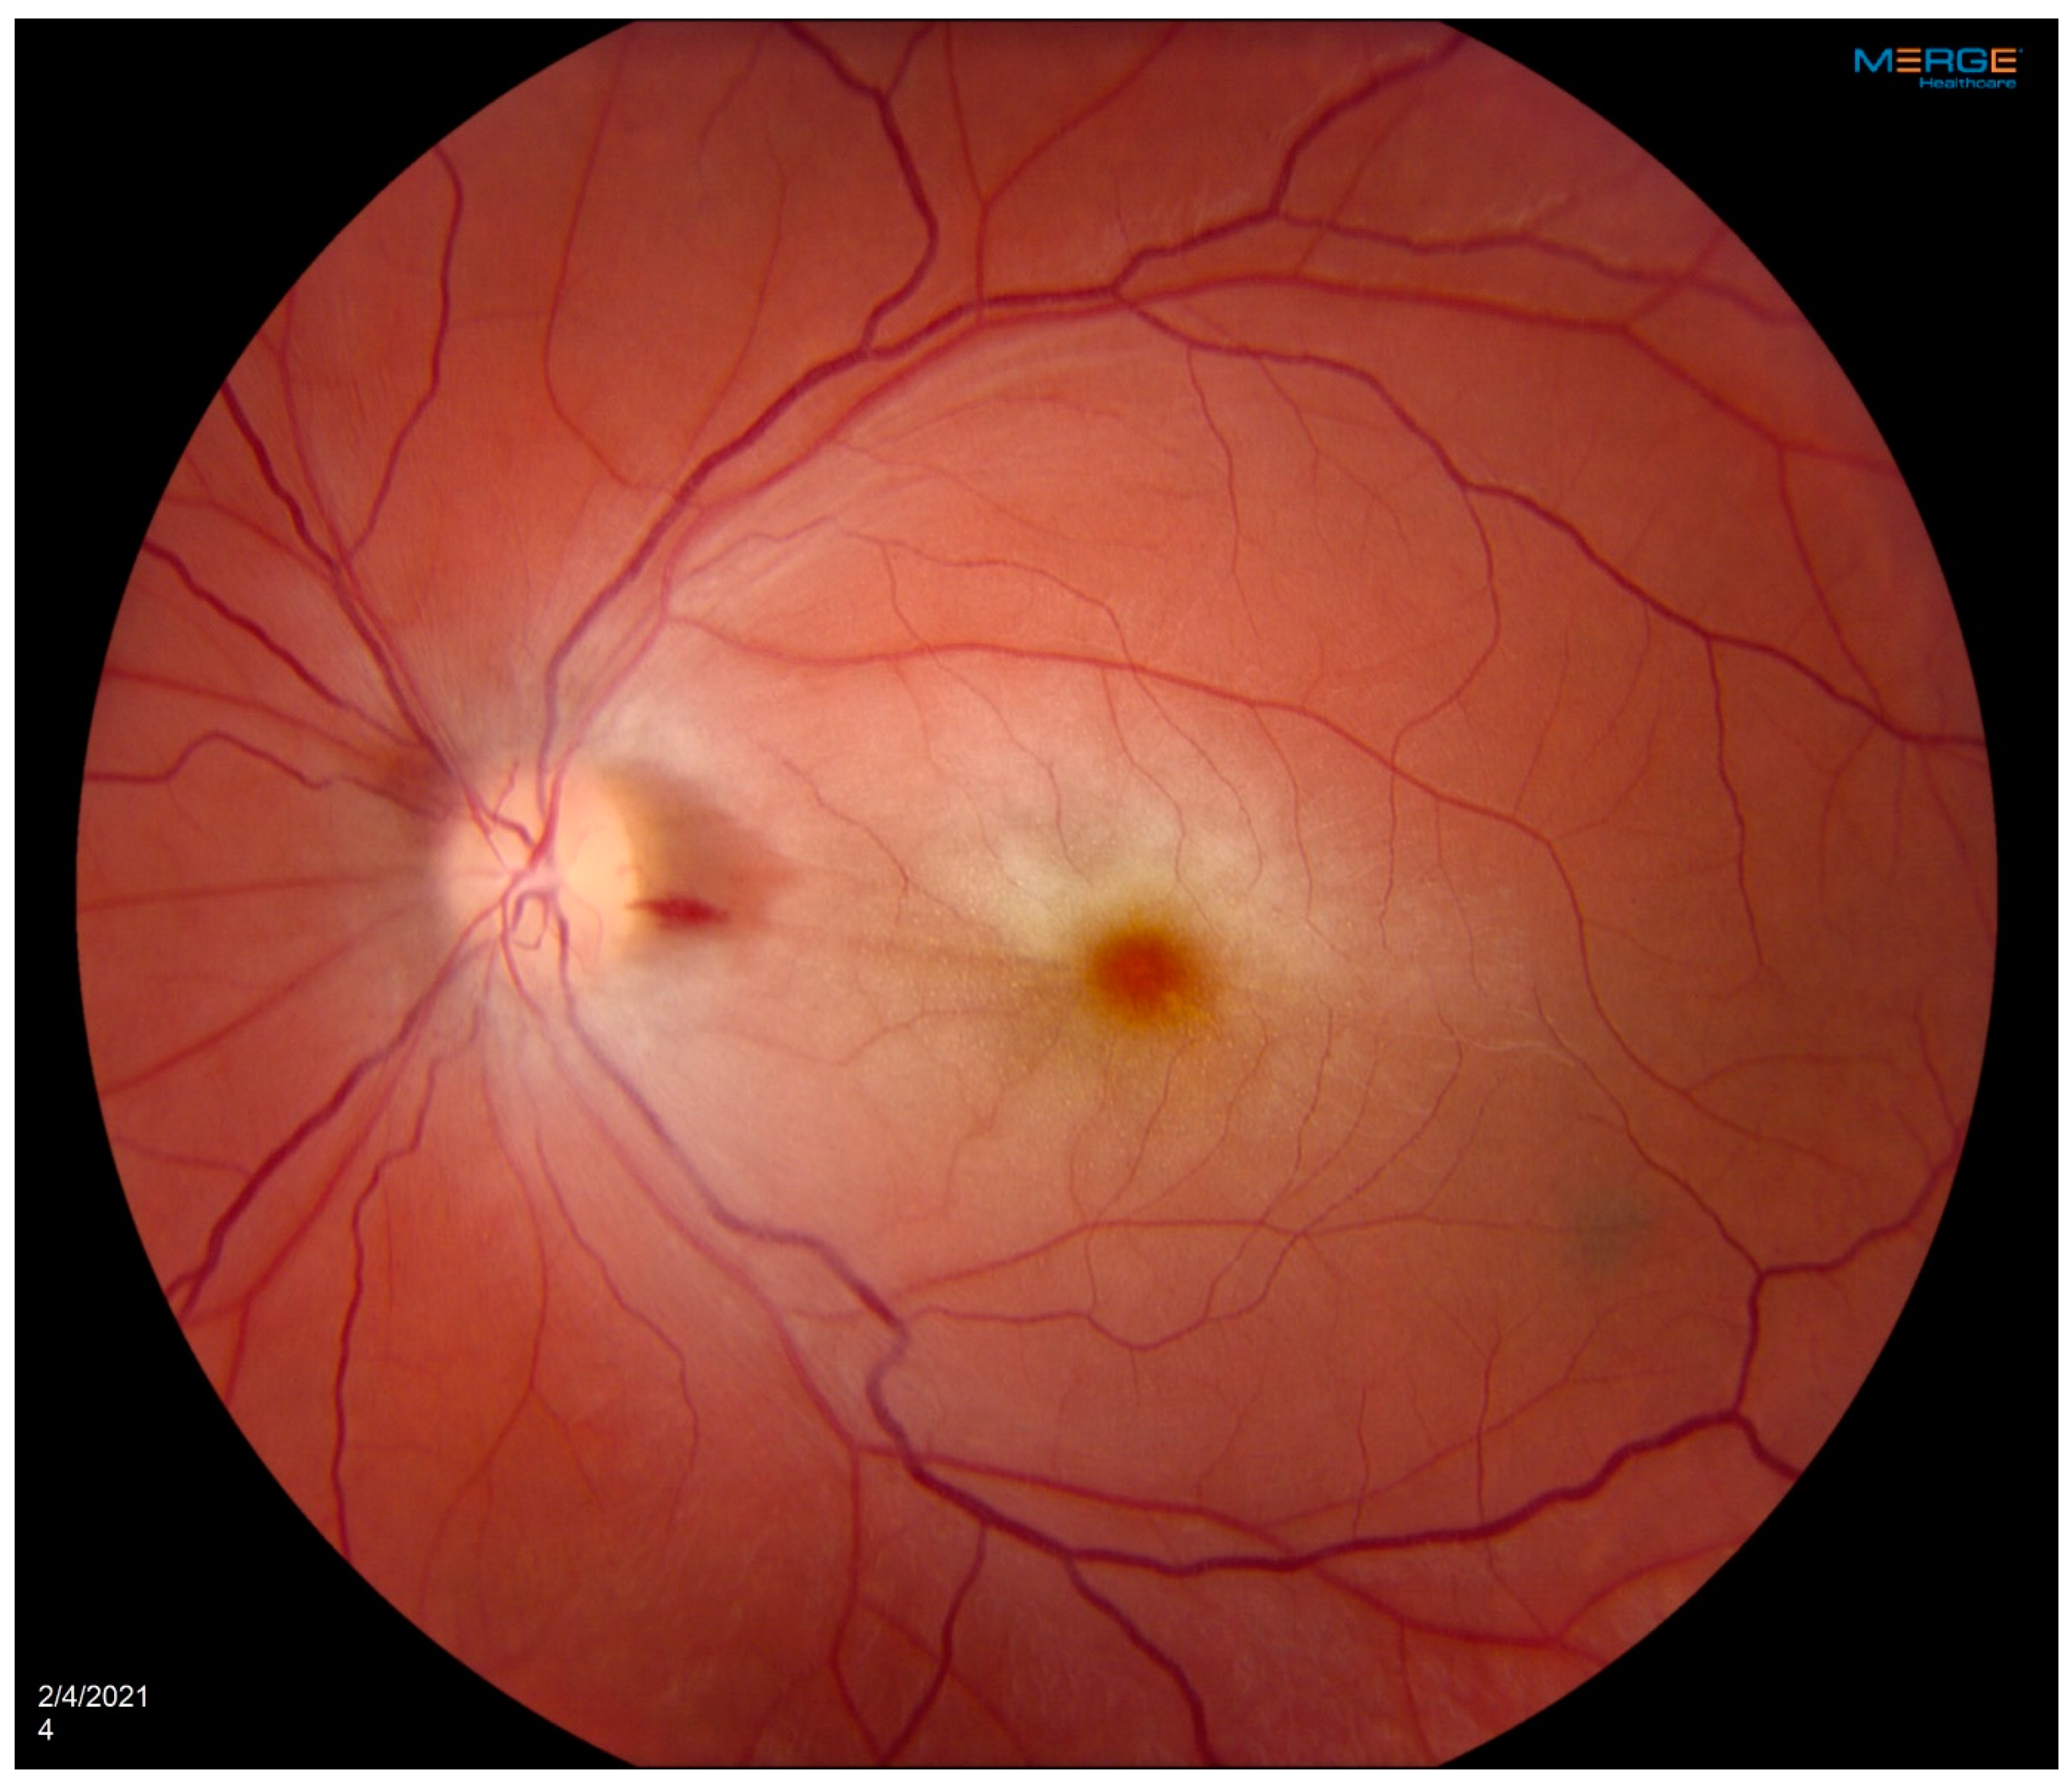

Central Retinal Artery Occlusion Associated with Takayasu Arteritis

Mumtaz, S.; Wilson, C.; Vibhute, P.; Eggenberger, E.R.; Berianu, F.; Abril, A. Central Retinal Artery Occlusion Associated with Takayasu Arteritis. Diagnostics 2024, 14, 1329. https://doi.org/10.3390/diagnostics14131329